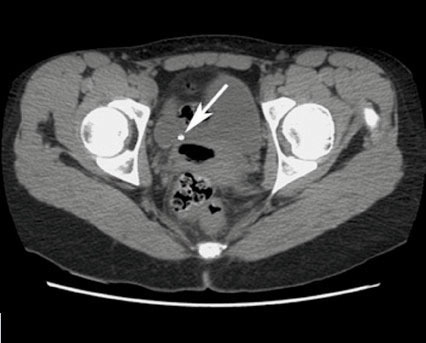

Vladimir Gomola, Jacques Hubert (La Revue du Praticien) Tomodensitométrie non injectée en coupe axiale montrant une lithiase du bas uretère droit au niveau de la jonction vésico-urétérale.